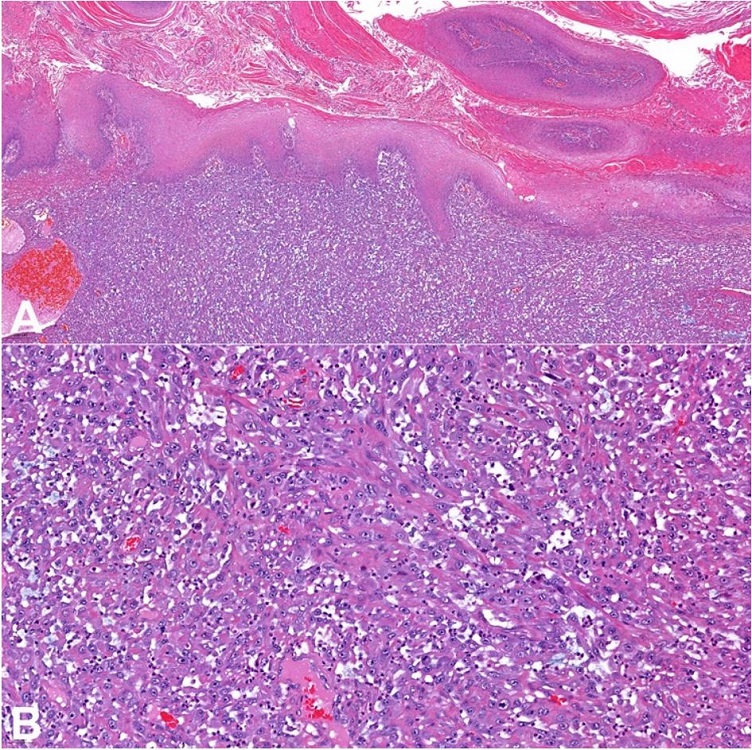

On the microscopic examination, the lesion showed two distinct areas. One area showed papillomatosis, with papillae of variable length without prominent fibrovascular cores. This component was well-differentiated, with cells showing bland, small, and round nuclei. The cells did not show koilocytosis. There was extensive hyper-parakeratosis and acanthosis. The tumor front was regular, broad, and pushing with a small focus of invasion (usual SCC type), consistent with verrucous hybrid carcinoma (Figure 2).

The other component was composed of atypical spindle cells arranged in vascularized bundles, mostly discohesive (Figure 3). These cells had enlarged and pleomorphic nuclei with conspicuous nucleoli and amphophilic cytoplasm. Mitoses were frequent, sometimes atypical, as well as areas of necrosis. The lymphovascular invasion was observed without perineural invasion. An inflammatory infiltrate with polymorphonuclear leukocytes and lymphocytes was also observed within the tumor. There was no mesenchymal differentiation. The morphologic features were consistent with a penile mixed SCC (verrucous hybrid-sarcomatoid carcinoma). The tumor compromised the cavernosum and spongiosum corpus. Surgical margins were free from tumor.